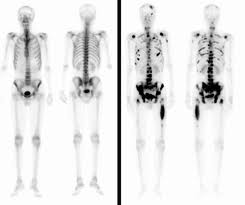

骨扫描骨转移

肺癌骨转移骨扫描图片

骨扫描骨转移报告图

骨扫描显示骨转移图片